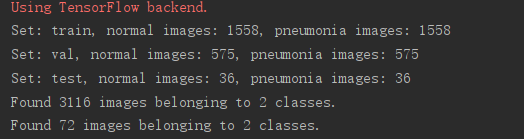

通过下载kaggle的Chest X-Ray Images (Pneumonia)数据集,其中一共包含5,863图像, 2种类别。当然还有其他数据集数据,例如ChestX-ray8数据集等。但是为了快速训练模型,我们随机选择了部分数据。其中包含训练集、验证集和测试集,其项目数据结构及数据统计如图所示(当大家的目的不是为了跑通模型,而是为了追求高准确率时,可以进行数据的合并):

| 数据样本 | 正样本个数 | 负样本个数 |

| 训练集 | 1558 | 1558 |

| 验证集 | 575 | 575 |

| 测试集 | 36 | 36 |